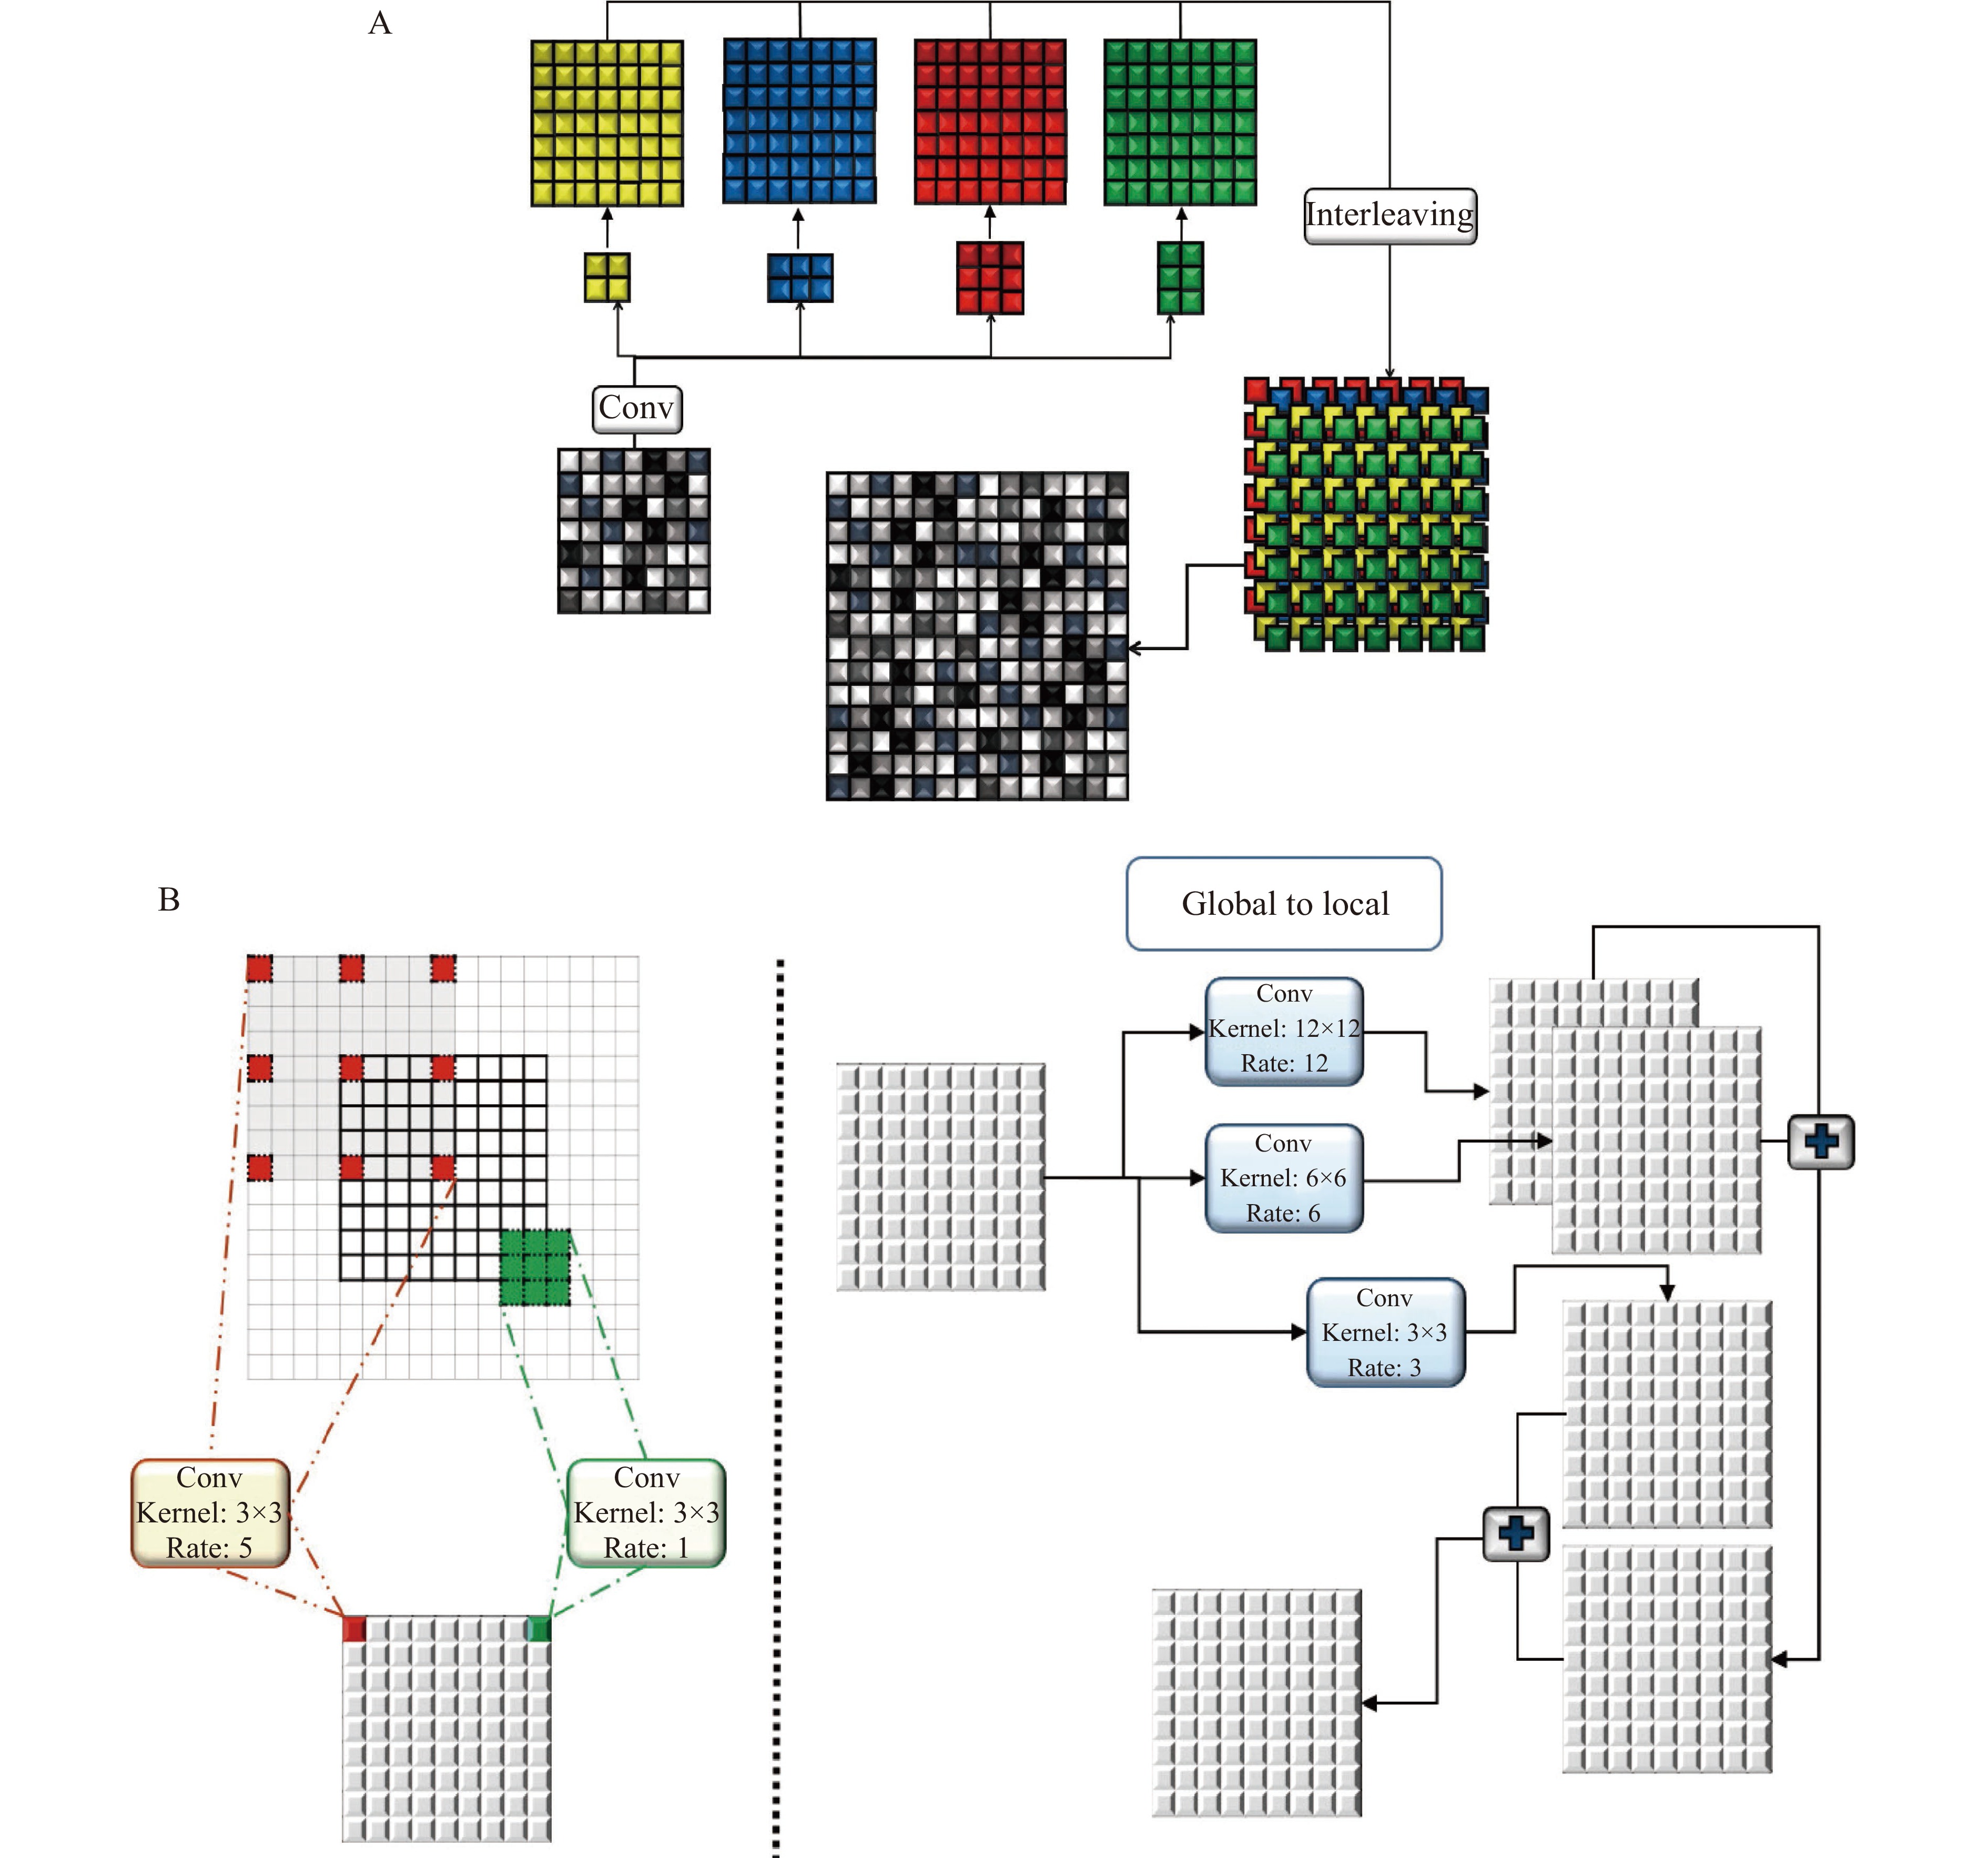

During decoding, generated coarse feature maps are transformed and the target image is gradually reconstructed from a low to high resolution. Reconstructing the target with a detailed image from the generated abstract low resolution is particularly difficult[20]. An up-sampling method is implemented to double the size of the feature maps at each level of the network. This method has two branches. In the first branch, four convolutional layers, 2×2, 3×2, 2×3, and 3×3, are applied to layers and results are interleaved to generate a feature map with doubled size. This procedure is repeated in the second branch with the difference that a 5×5 convolutional layer is applied. Finally, the results of the first and second layers are fused (Fig. 3A).

Estimating target images using an image with a different domain is a complex task that requires local and global information from the input image, simultaneously. Context information of different scales should be fused to model the dependency between different tissues and their surroundings in medical images. Hence, a global-to-local feature fusion strategy is proposed to address this issue (see Fig. 2). This strategy is based on the dilated convolutional operation[21], which makes it possible to expand the receptive field without increasing the number of parameters (Fig. 3B). The general form of discrete convolutions is defined according to equation (1):

In the proposed strategy, a series of dilation rates (3, 6, and 12) is selected and employed to produce multi-scale feature maps. After applying dilated convolution, the size of generated feature maps should remain unchanged, which requires carefully selecting a padding rate in accordance with the dilated rate. The higher the dilation rate, the more general the information contained will be, with wider visual cues in the produced feature maps. Therefore, generated low and high-level context information is progressively aggregated. This procedure is carried out using the highest level of context information which is produced by the largest dilated rate to the lowest-level feature maps that are produced by the smallest dilated rate (ln). The procedure of extracting and fusing (